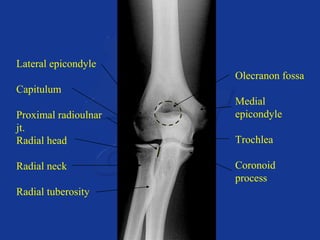

Lateral epicondyle

Capitulum

Proximal radioulnar

jt.

Radial head

Radial neck

Radial tuberosity

Olecranon fossa

Medial

epicondyle

Trochlea

Coronoid

process